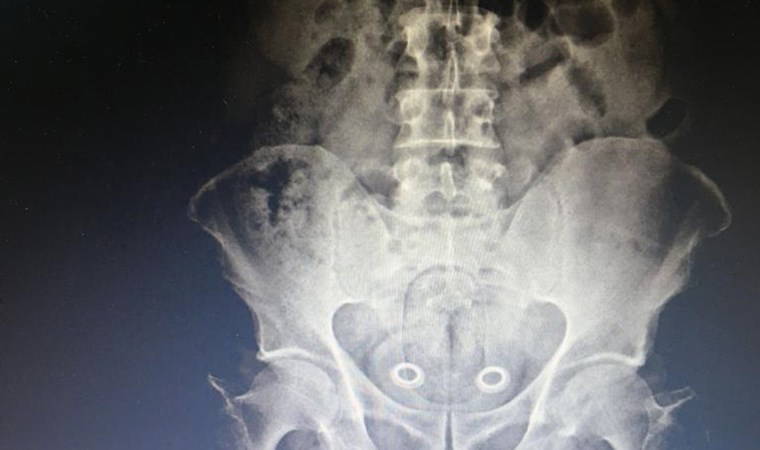

Kars'ta, polis tarafından gözaltına alınan İran uyruklu şüphelinin çekilen röntgen filminde bağırsağında uyuşturucu taşıdığı ortaya çıktı. İran uyruklu bir kişinin, uyuşturucu taşıdığı bilgisi üzerine harekete geçen Kars Emniyet Müdürlüğü Narkotik Şube Müdürlüğü ekipleri, plakası belirlenen aracı Digor yolu üzerinde durdurdu.

İran uyruklu A.P. (47) ve N.Ş. (24) isimli kadın ile Türk vatandaşları Ö.A. (25), M.Y. (36) ve Ş.K. (34) gözaltına alındı. Araçta narkotik köpeği Odin’le yapılan aramada uyuşturucu bulunamazken bir adet tabanca ile 6 fişek ele geçirildi. İranlı şüpheliye götürüldüğü hastanede röntgen filmi çektirildi. Röntgen filminde, şüphelinin bağırsağında uyuşturucu taşıdığı belirlendi. İlaçla, İranlı'nın bağırsaklarındaki 110 gram metamfetamin ve  0,64 gram esrarı çıkarması sağlandı.

Şüphelinin narkotik köpeğine yakalanmamak için uyuşturucuyu bağırsaklarında gizlediği öğrenildi.